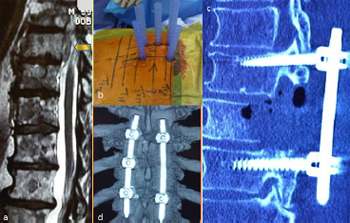

Fig. 12. Illustrative patient 2, a 69-year-old male who presented with progressive

paraparesis and cord compression at T9. (a) Sagittal T2-weighted MRI showing T9

cord compression from lung metastasis (arrow); (b) intra-operative photograph

showing percutaneous screw fixation; (c) sagittal post-operative CT scan reconstruction

showing partial vertebrectomy and decompression; and (d) post-operative

three-dimensional CT scan reconstruction showing stabilisation.

5.3.1. Illustrative patient 3

A 69-year-old male presented with progressive paraparesis and

cord compression at T9. He had metastatic lung cancer with an expected

longevity of less than 12 months. MIS decompression was

proposed; however, stabilisation was recommended due to the

anterior compression and pediculectomy/partial vertebrectomy

necessary for adequate tumour resection. Surgical time was 2

hours and 35 minutes with 210 mL of blood loss and a length of stay (LOS) of 5 days. The patient remained independently mobile

until his death 7 months following surgery.